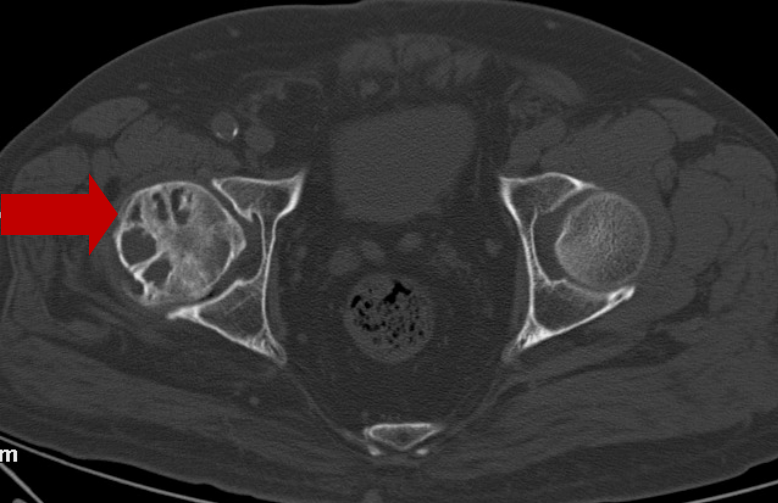

2022年7月11日CT:

左股骨头坏死区缩小,

周围骨质明显生长、修复。

2022年7月进行复查展示,曾经的股骨头坏死的区域显著地变狭小,囊肿变化趋向减小;处于关节处含有液体、骨髓出现水肿的情况极大程度地减轻。现如今没显著特有的不舒服,能够正常地生活。